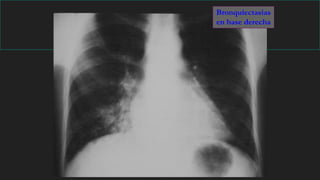

Bronquiectasias

en base derecha

Semiología de las bronquiectasias

A

A. Normal

B

C

D

E

B. Quistes de pared fina

C. Quistes de pared

gruesa

D. Ocupación parcial:

“Nidos de golondrina”

E. Ocupación completa:

Nódulos